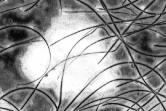

From the fuzzy sets , and three grey probability images are generated , and of in size and a greyscale in . These are defined as follows: , , and

. Evidently, ,

.

These probability images show the pixel probabilities in graphic format, also taking advantage of the fact that as there are three images, a color image can be built by assigning the to the red channel, to the green channel and to the blue channel. This new image is equivalent to the three probability images and enables the result of the fuzzy classification of pixels to be seen much more clearly in graphic format, all of which is shown in Fig. 3.